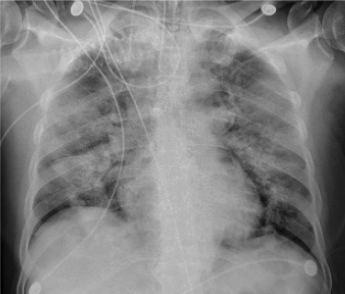

(RSNA) Case example of diffuse non-specific airspace opacities in both lungs in an intubated patient with confirmed COVID diagnosis on day 6 post admission. Key pertinent negative findings include the following: No pleural effusions; No lymphadenopathy; No cardiomegaly; No interstitial opacities to suggest pulmonary edema. (Ref: Song, et al, Radiology 2020)